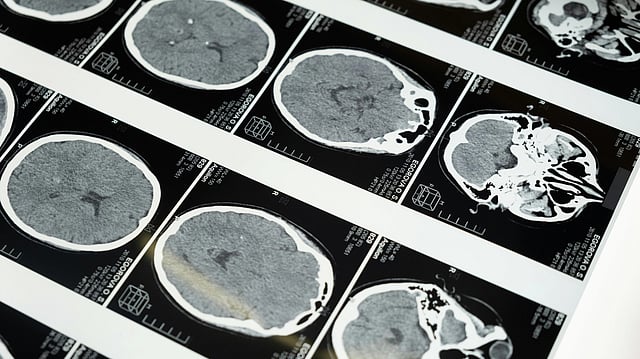

Focused ultrasound with microbubbles can safely and temporarily open the blood–brain barrier to treat brain tumors and neurodegenerative disorders. cottonbro studio/ Pexels

Focused ultrasound combined with microbubbles is increasingly being used to safely and reversibly open the blood–brain barrier (BBB) for the treatment of brain tumors and neurodegenerative disorders. While much attention has been placed on acoustic pressure and total exposure time, less is known about how the temporal structure of ultrasound delivery influences microbubble activity.

In a recently published study, researchers from the Institute of Fundamental Technological Research at the Polish Academy of Sciences systematically examined how ultrasound parameters (i.e., pressure, pulse duration, and microbubble concentration) shape acoustic cavitation signals, which are widely used to guide BBB opening. Using a controlled flow model, the authors confirmed known trends, such as optimal pressure windows for stable cavitation and the strong influence of microbubble concentration on acoustic emissions.

A particularly interesting finding was that the number of ultrasound pulses delivered can significantly affect cavitation behavior even when total “on-time” is similar. This suggests that effective sonication time alone may not fully describe the dose experienced by microbubbles. Instead, pulse history – how many times bubbles are excited – may play an underappreciated role in how cavitation evolves during treatment.

These results are relevant to BBB opening strategies that rely on real-time acoustic feedback, reinforcing the idea that how ultrasound is delivered can matter as much as how long. At the same time, the study was performed in a simplified experimental system, and many effects were most clearly observed at microbubble concentrations higher than those typically achieved in vivo, especially during clinical infusion protocols. Blood flow, vessel size, and replenishment dynamics were not varied and remain important factors for translation.

Overall, this work provides mechanistic insight into microbubble behavior and highlights pulse structure as a potential consideration for refining focused ultrasound–mediated BBB opening while underscoring the need for continued in vivo validation under clinically realistic conditions.